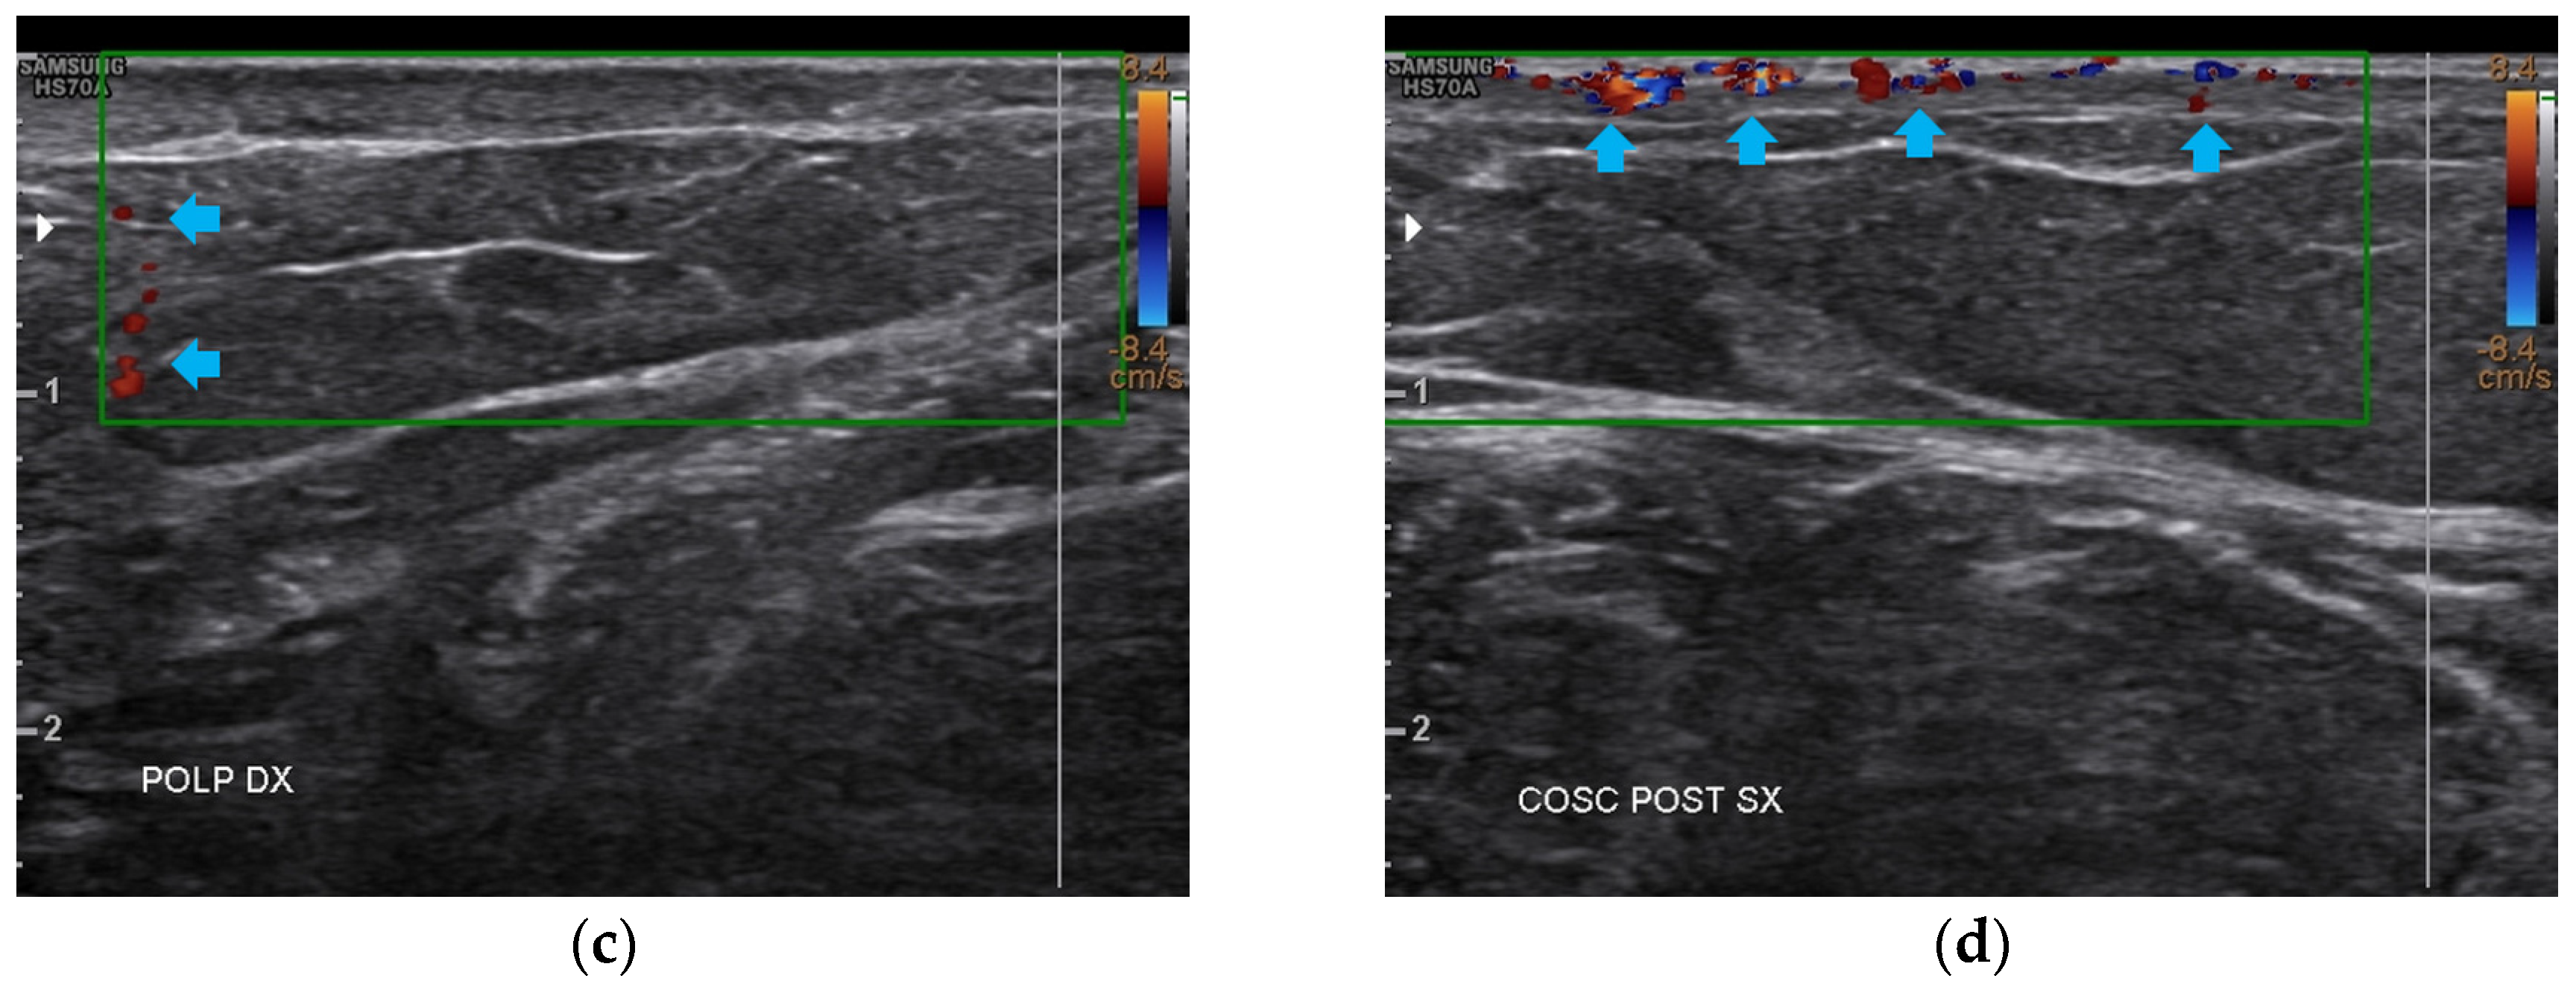

3.1. Basal Imaging Evaluations